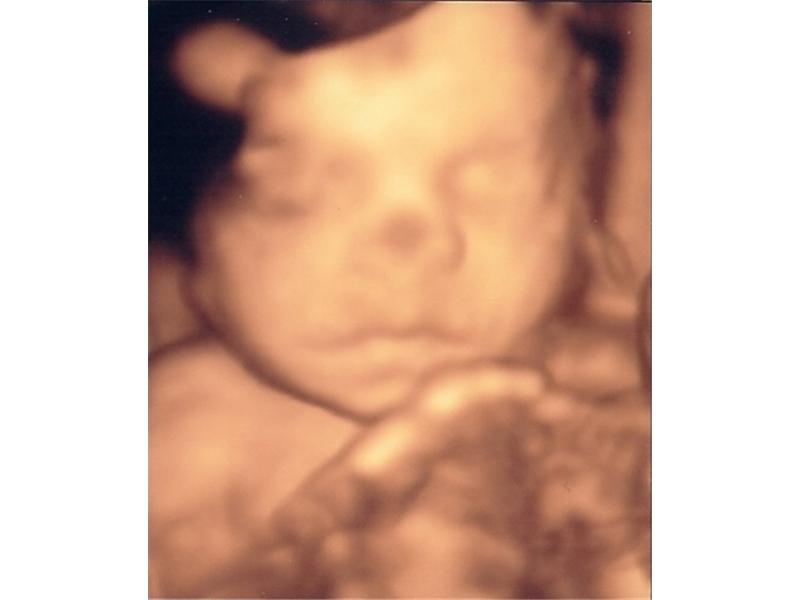

Tak na tohohle výtržníka teď všichni čekáme. Snad se pan doktor nepřehlédl a bude to kluk. Jinak je název téhle galerie tak trochu mimo 😀

Zdroj: archiv redakce